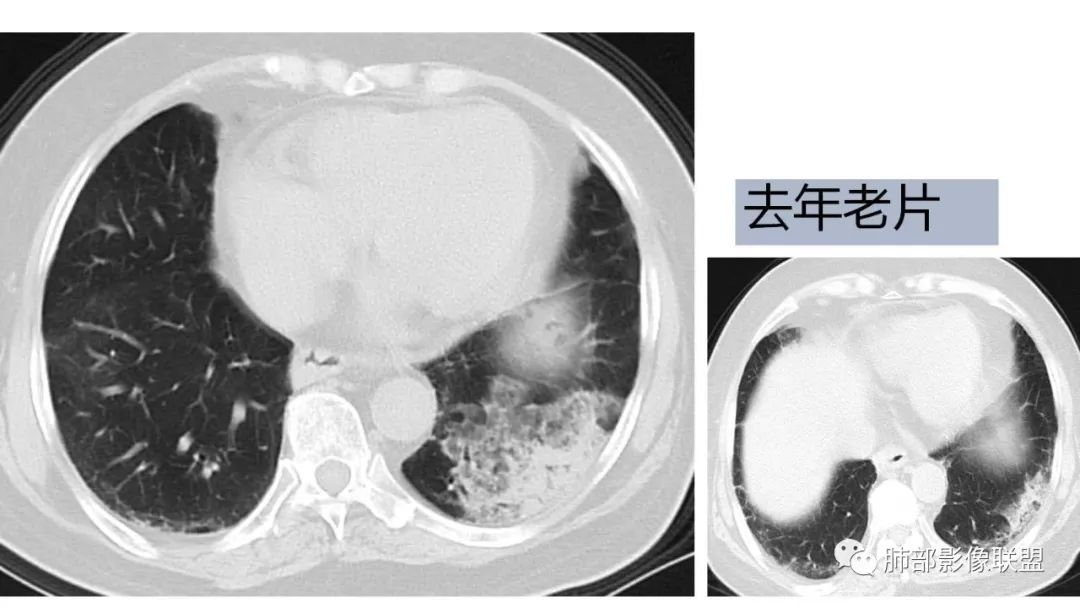

9.粘液腺癌的变化规律:结节缓慢发展而来,向周围播散形成斑片后可快速进展,有时支气管镜后或粘液排出后局部可形成好转的假象。病灶可沿肺泡和支气管播散。

三、本例是一个误诊多年的病例,给我们很多启示:

2.粘液腺癌易伪装成肺炎的形态,尤其是当患者本身具有免疫色彩的时候,易误诊为间质性肺炎,或肺部感染。若治疗无效,取得病理很重要。

4.回到本例,左下肺病变两次好转,均未经过肿瘤治疗,第一次是支气管镜后,第二次是当其他病变都在进展的情况下,左下肺病变范围反而缩小趋于浅淡。